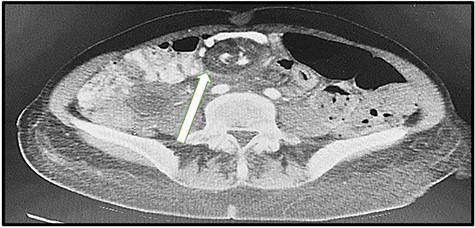

We found trapped dilated and twisted jejunal loops at a defect between the Roux limb and the mesentery of the transverse colon, which is most likely Peterson’s space (Fig. 3). The trapped bowel was untwisted and release. We found no evidence of gangrene nor perforation, only a little amount of clear fluid in the pelvic.

Peterson’s defect found behind the Roux limb and the mesentery of the transverse colon.